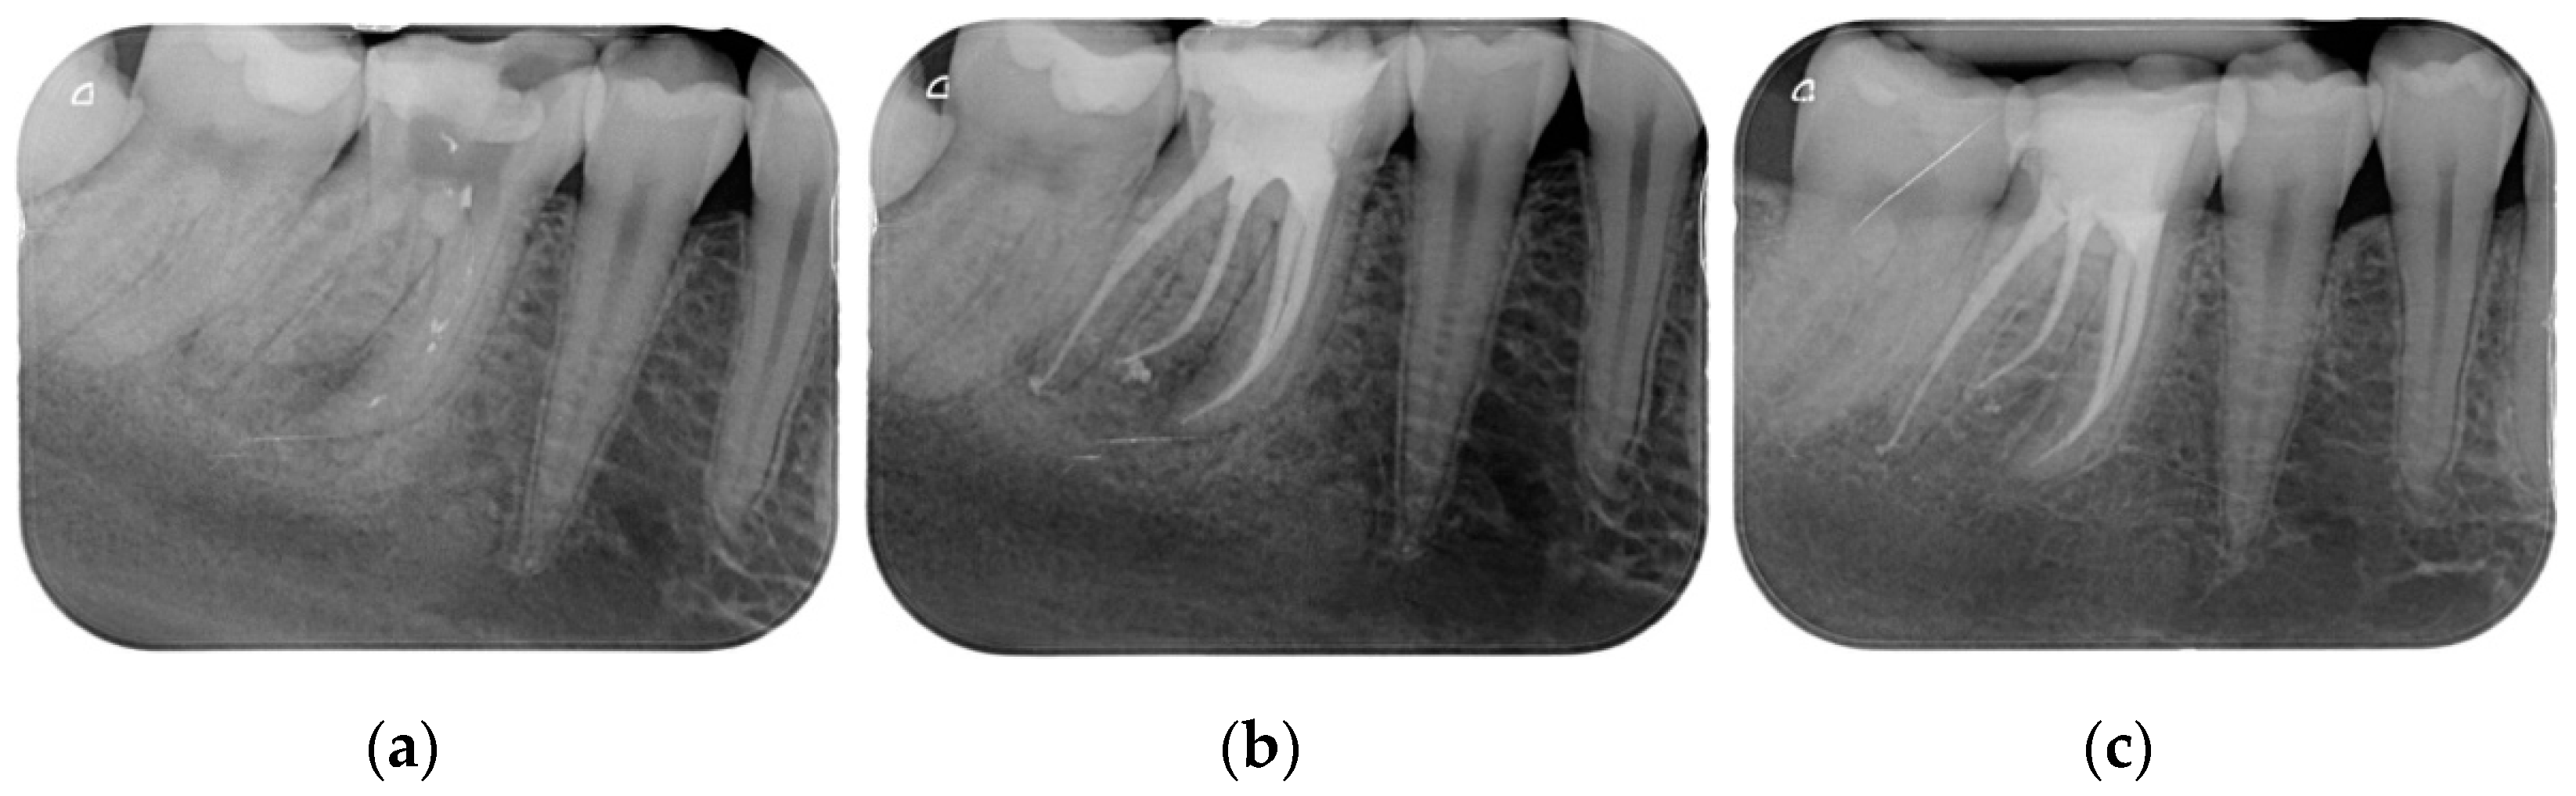

Results showed that 92.61% of ETT did not have any complications up to 18 years (Figure 1, Figure 2 and Figure 3).

Regarding the quality of root filling, 264 teeth (88.59%) showed good filling (Figure 1, Figure 2 and Figure 3) (gutta-percha at the radiologic apex), 22 roots (7.38%) short filling (shorter than 1 mm from the radiographic apex), and 12 (4.03%) long filling (longer than 1 mm of the radiographic apex).

Figure 1. (a) Upper central incisor with periapical lesion. (b) The root after being endodontically treated. A second root was filled by warm gutta-percha technique. A direct resin composite restoration was used to restore the coronal part of the tooth. (c) The root after 3 years of clinical service. A complete healing is evident.

The numbers of failures due to tooth fractures, endodontic, periodontal, or prosthodontic reasons, were limited to 22 of 298 ETT. Of the recorded failures, 14 were reported as repairable; eight were catastrophic failures and, consequently, needed root extraction. The success rate was around 92% (Figure 1, Figure 2 and Figure 3), the survival rate around 4.69%, and only less than 2.69% were irreversible failures. The success and survival rates of this clinical study were a little higher than several others [36,37,38]. Another important aspect related to the failure was the fact that irreversible failures mainly took over in the first two years and within the first 5 years, when cumulated as reversible and irreversible failures. It can be speculated that “biological” complications can come out rather quickly, and periodontal and prosthodontic complications in a longer time, but after 5 years of clinical service, it can be expected that an ETT can stay in clinical service for many more years.